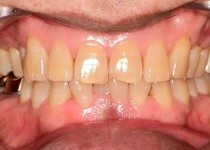

치아미백

스탠다드 미백(오스템 뷰티스)

스탠다드 미백 (오스템 뷰티스)